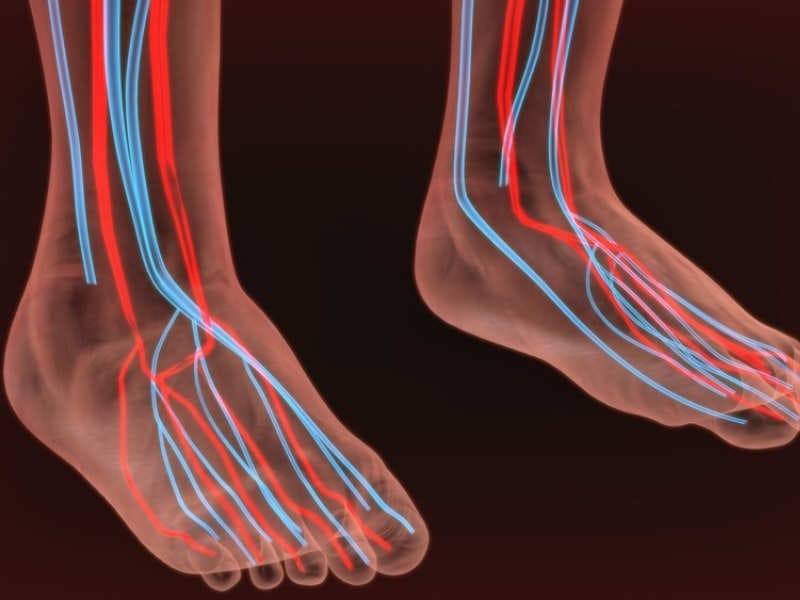

FORTU FLEX оказывает всестороннее оздоровляющее действие на костную и хрящевую ткани, синовиальную жидкость, мышечные волокна, на ткани связок, сосудов и сухожилий, находящихся в стопе каждого человека.

НОРМАЛИЗУЕТСЯ КРОВООБРАЩЕНИЕ и обменные процессы в суставах и окружающих тканях;